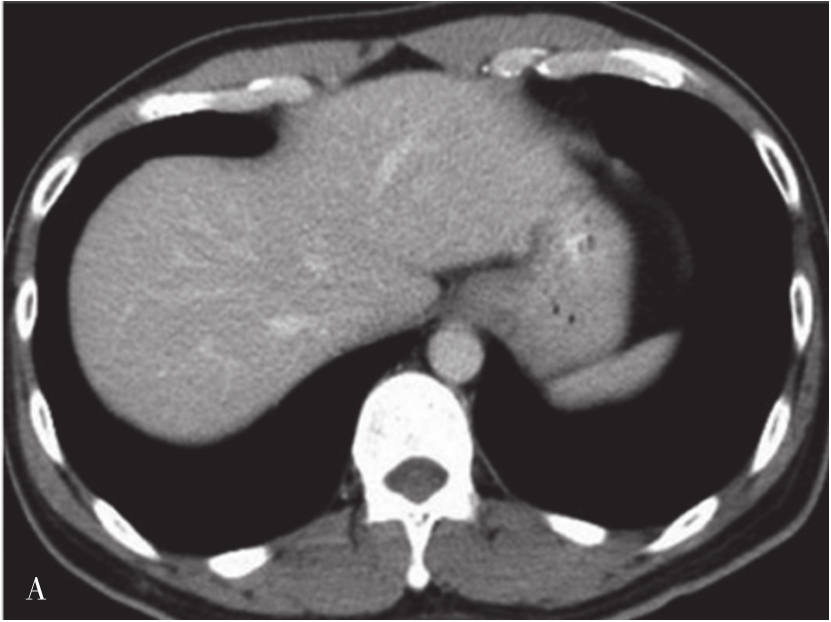

(1)肝脏大小、形态:

在不同层面CT横断面图像,肝脏形态各异。在靠近横膈肝顶部,呈类圆形或椭圆形,面积小,占据腹腔的右半(图5-21-36A);在肝中部或肝门附件,近似楔形,面积较大,占据右侧腹腔(图5-21-36B);在肝下部形态类似于梭形或半月形(图5-21-36C)。

图5-21-36 正常肝脏CT表现

(3)肝脏实质密度:

正常肝实质密度较均匀,平扫CT值范围为40~70HU,高于脾脏、胰腺、肾脏,主要是因为肝细胞内含有高浓度糖原的结果。脂肪肝时平扫CT值低于脾脏。增强扫描能清楚显示肝左、中、右静脉及门脉主干及肝内主要分支,这些血管强化呈高密度影。门脉主干由肠系膜上静脉和脾静脉汇合而成,汇合点位于胰腺头部和颈部交界后方,向右上方斜行,通过肝十二指肠韧带进入肝门,分为门脉左右支入肝。

CT显示肝脏与周围脏器关系优于其他影像学检查。肝脏左侧脏面有胃以及胰腺等器官毗邻;右侧脏面有下腔静脉、十二指肠、胆囊、横结肠、右肾及右肾上腺等器官毗邻。在肝脏轮廓上可呈现这些脏器相应压迹。